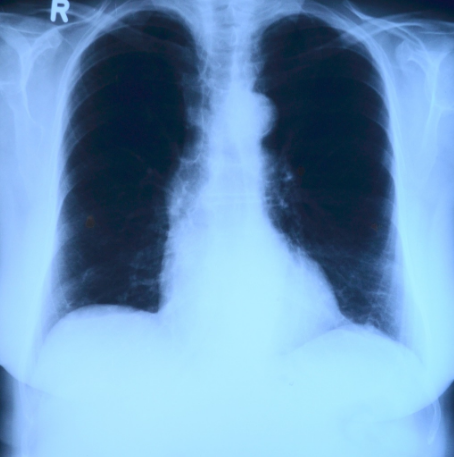

폐렴은 공기 중에 존재하는 세균 또는 바이러스를 통해 감염되는 심각한 호흡기 질환입니다. 이 질병은 기침, 가래, 고열 및 호흡곤란과 같은 다양한 증상을 유발할 수 있습니다. 폐렴은 특히 어린 아이, 노인, 만성질환 환자 및 면역곤란 환자들에게 위험합니다. 폐렴은 심각한 경우 호흡 곤란과 사망으로 이어질 수 있으므로 폐렴의 위험성을 인지하는 것이 중요합니다.